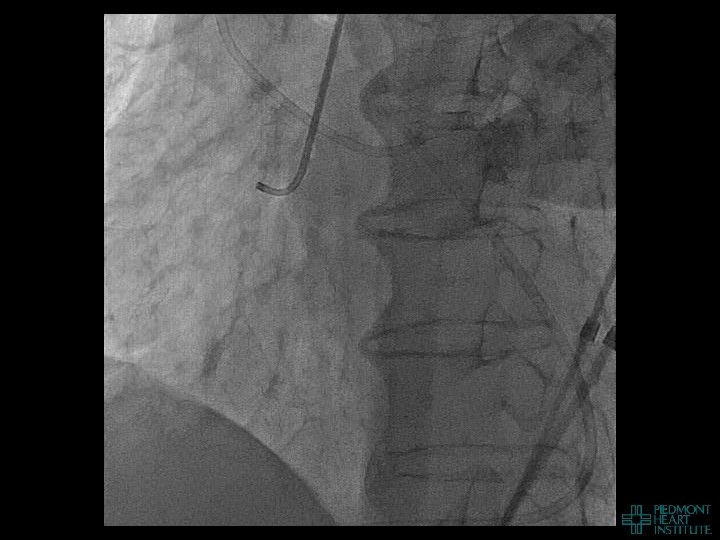

Case Example 2